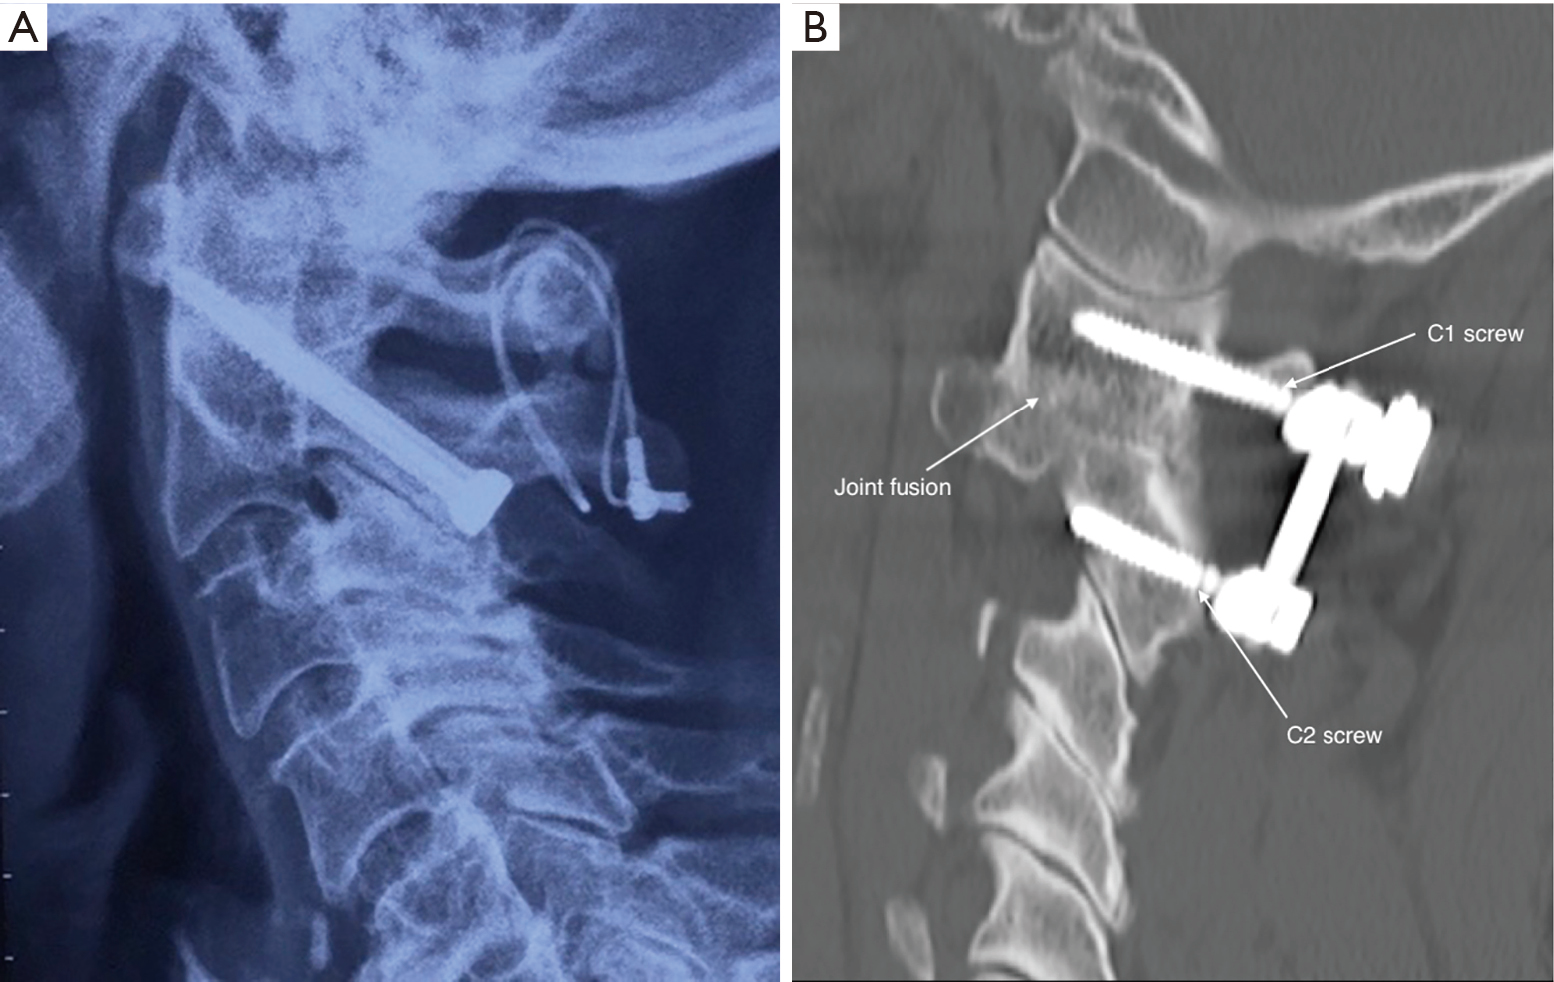

Kegiatan tersebut merupakan kegiatan yang melibatkan kemampuan mengingat sesuatu sehingga masuk dalam ranah. A (wajib))/ b (wajib) / c (peminatan : Maka indikator c1, c2 dilakukan dengan luring, sedangkan c3 dan c4 dilakukan dengan tatap muka langsung atau tatap muka maya (daring) b. Contoh soal c1 c2 c3 c4 c5 c6 matematika smp. 1100 patients who have been operated in our department for cervical disc herniation between 2000 and 2009 were studied retrospectively. C1, c2, c3, c4, c5, dan c6 evaluasi pembelajaran.

C1,c2,c3 dan silabus smk kurikulum 2013. Baiklah kami ingin memberikan contoh penerapan soal c1 c2 c3 c4 c5 dan c6 yang terdiri dari 3. Berdasarkan struktur kurikulum 2013 ini maka disusun sebagai berikut : Iii / 1 tahun pelajaran : 1100 patients who have been operated in our department for cervical disc herniation between 2000 and 2009 were studied retrospectively.

Menurut anda apakah produk yang anda beli termasuk ke dalam lucky box 06.41 mgmp pemasaran yogyakarta contoh rpp ini diambil dari berbagai sumber. Dalam ranah kognitif c1 siswa melakukan aktifitas “bertanya jawab”. (c1) kombinasi menjelaskan (c2) kombinasi menentukan (c3) kombinasi menganalisis (c4) kombinasi penilaian pengetahuan 1100 patients who have been operated in our department for cervical disc herniation between 2000 and 2009 were studied retrospectively.